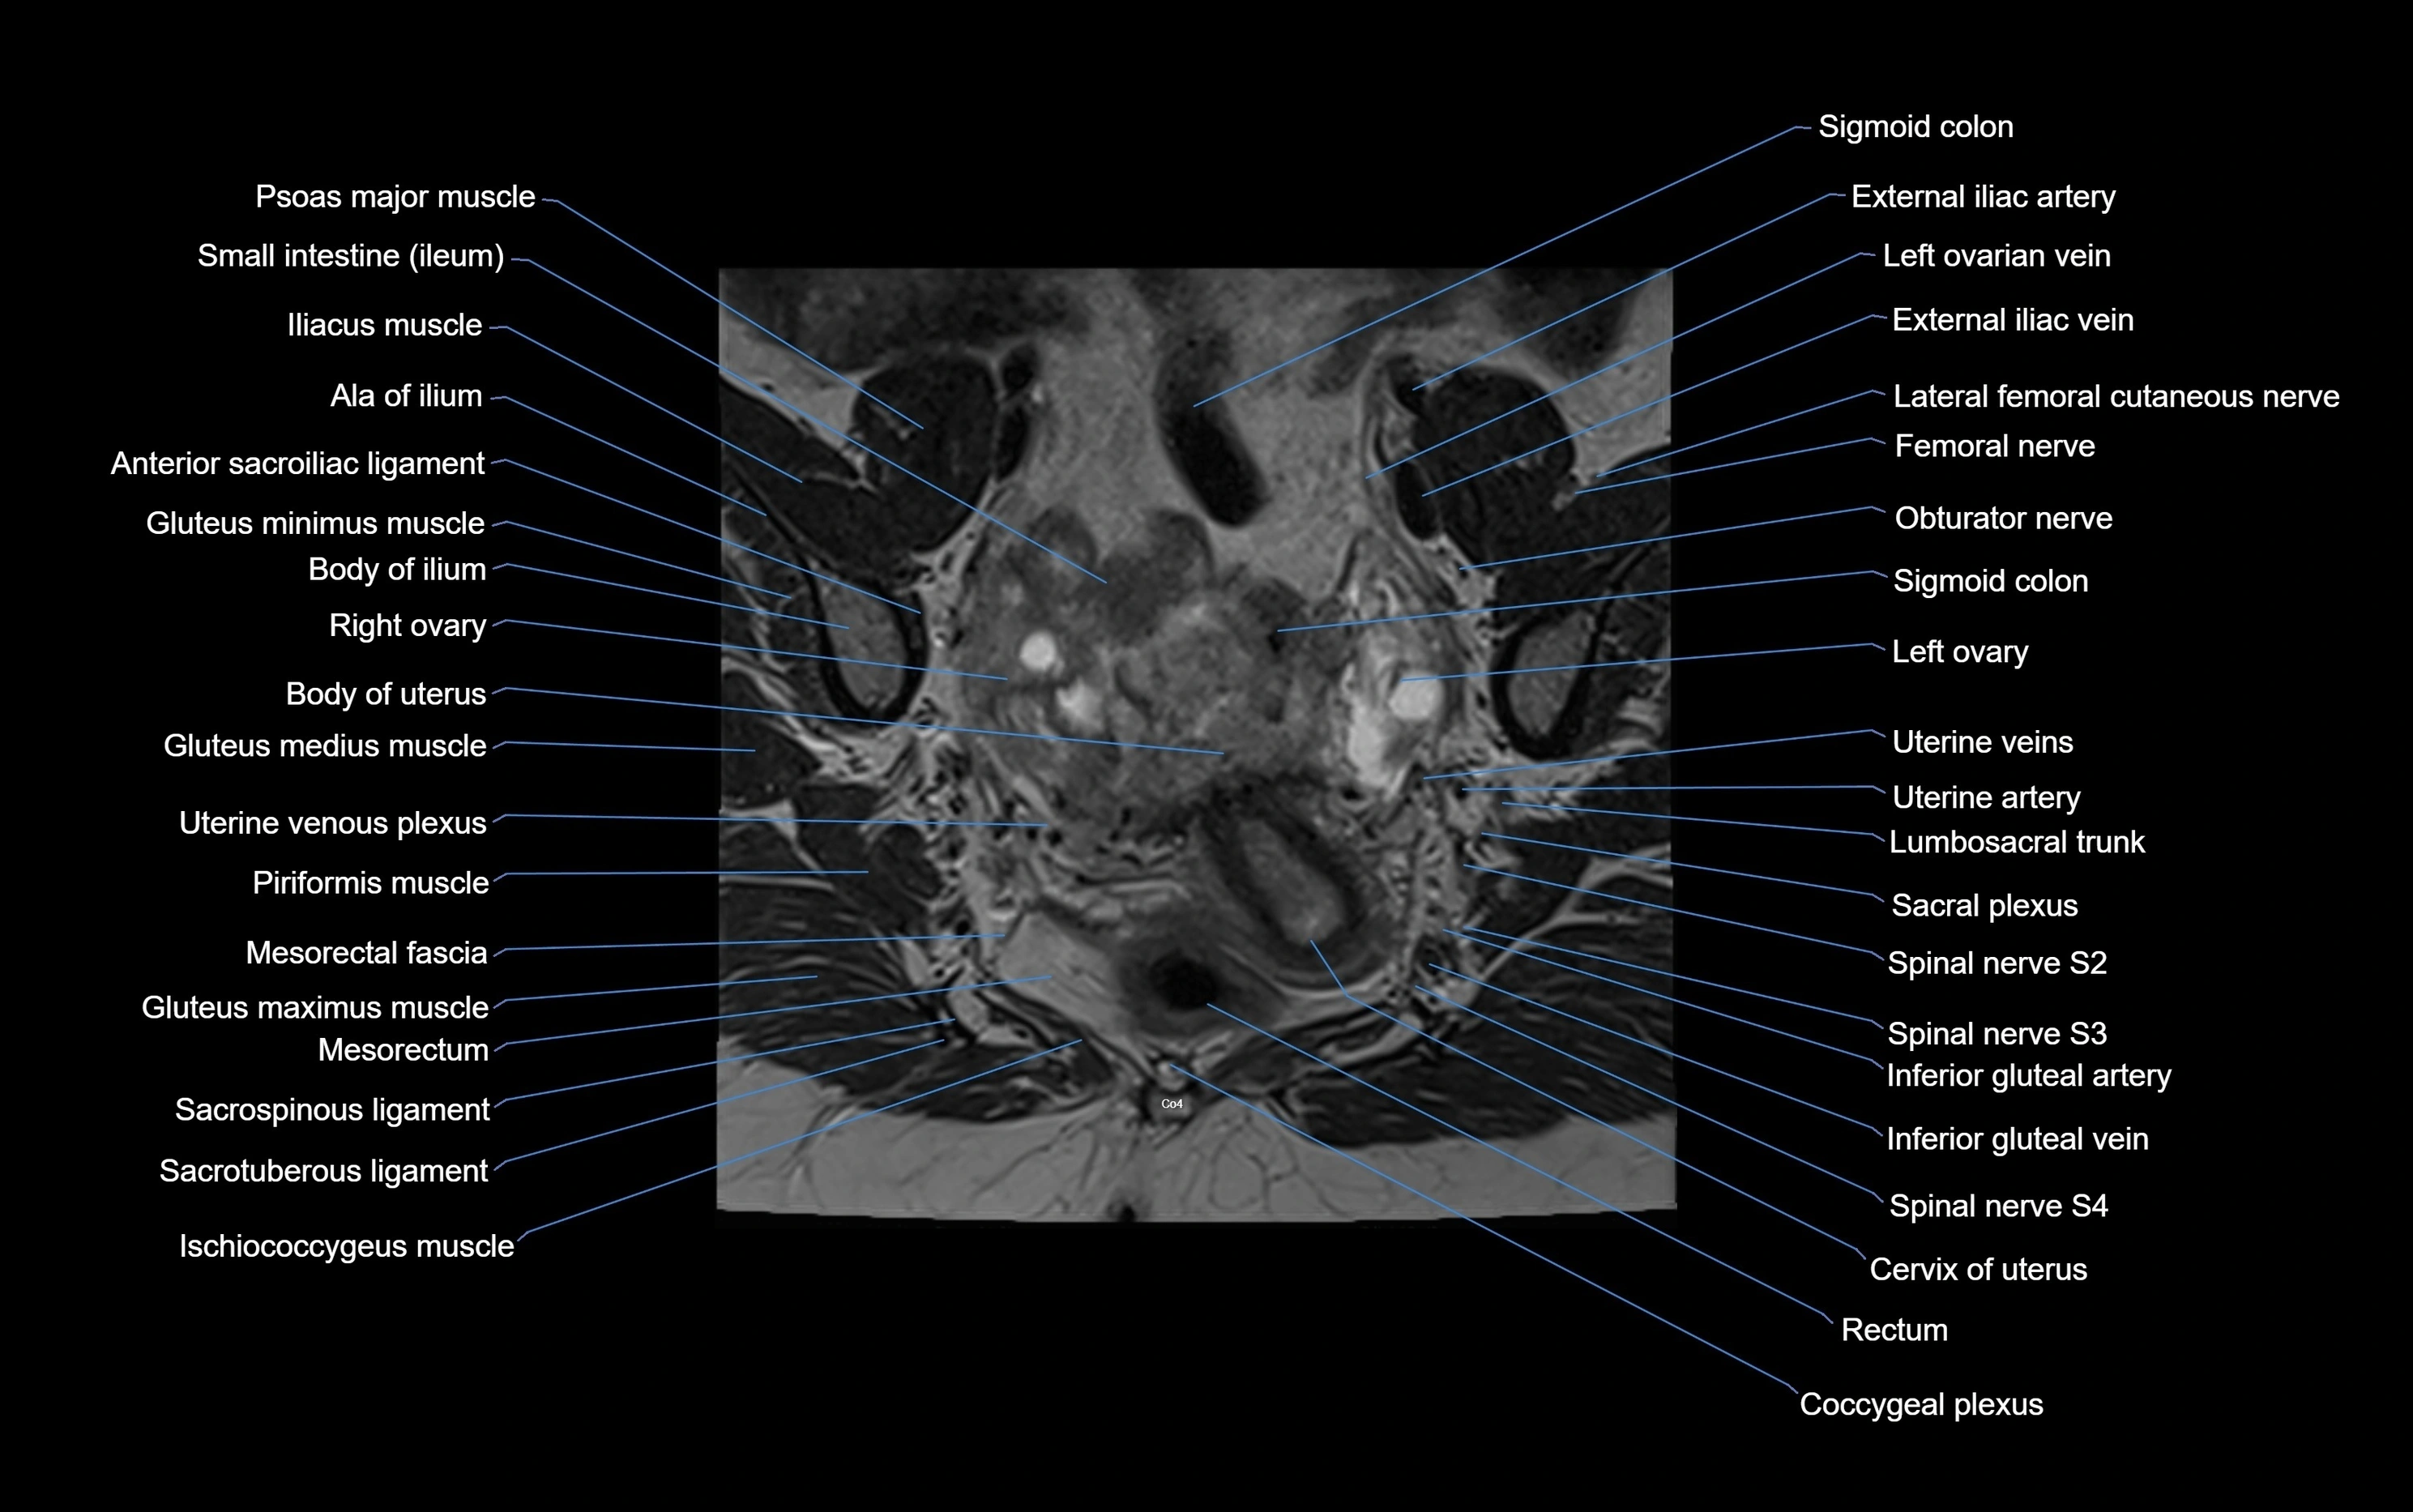

MRI image

image